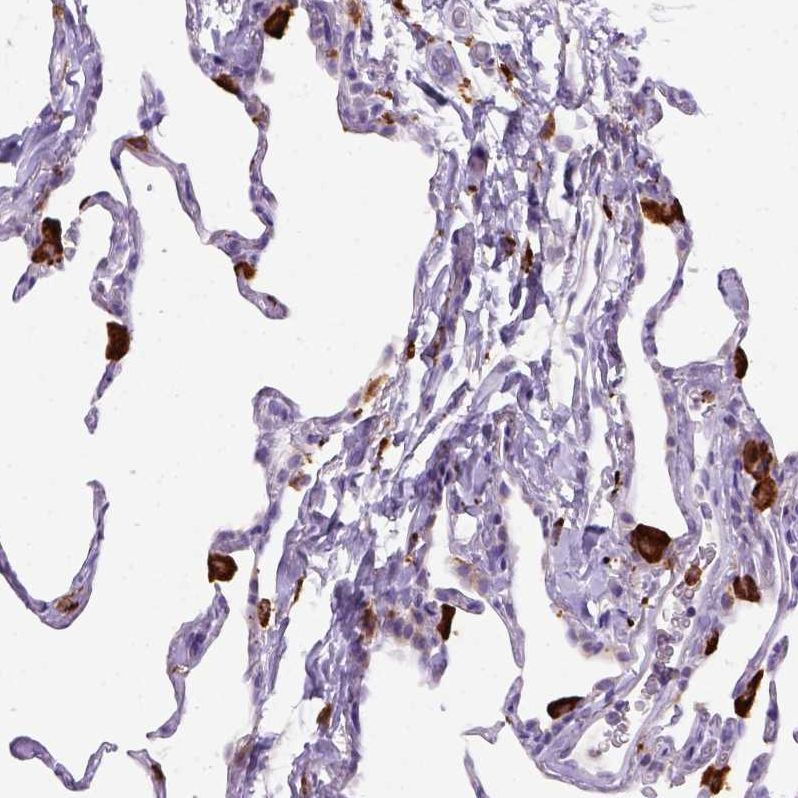

Immunohistochemistry analysis in human lung and skeletal muscle tissues using AMAb90874 antibody. Corresponding CD68 RNA-seq data are presented for the same tissues.